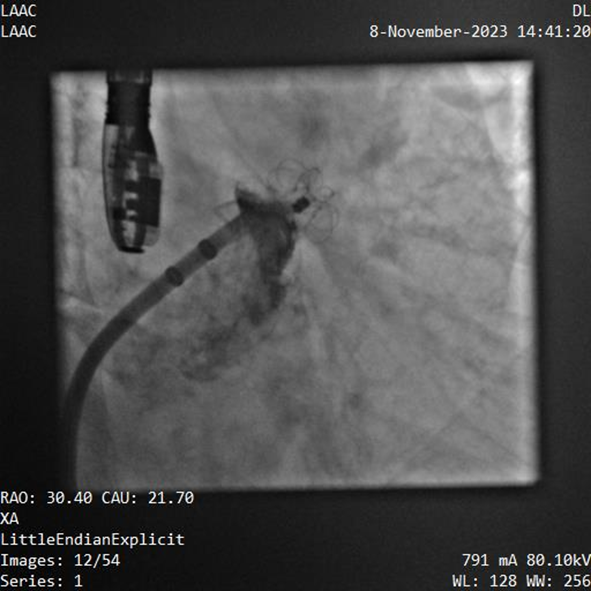

器械釋放后造影示封堵器展開(kāi)良好,封堵完全